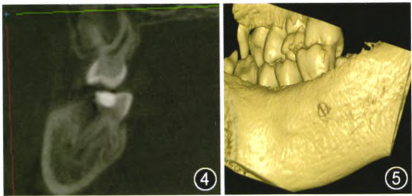

随后进行锥形束CT检查发现患者右颌下区及颏下区软组织内出现局限性蜂窝状透影区(见图3);

图3.png

右下第一恒磨牙远中舌根根尖1/3向颊侧弯曲,角度较大(接近90°);弯曲处相应舌侧骨板缺如(见图4、5)。

1个月后以牙胶尖+糊剂对患牙进行根管充填,再次进行锥形束CT检查显示,根管弯曲相应舌侧骨板缺如处根充糊剂超出根管,说明此处根管侧穿。